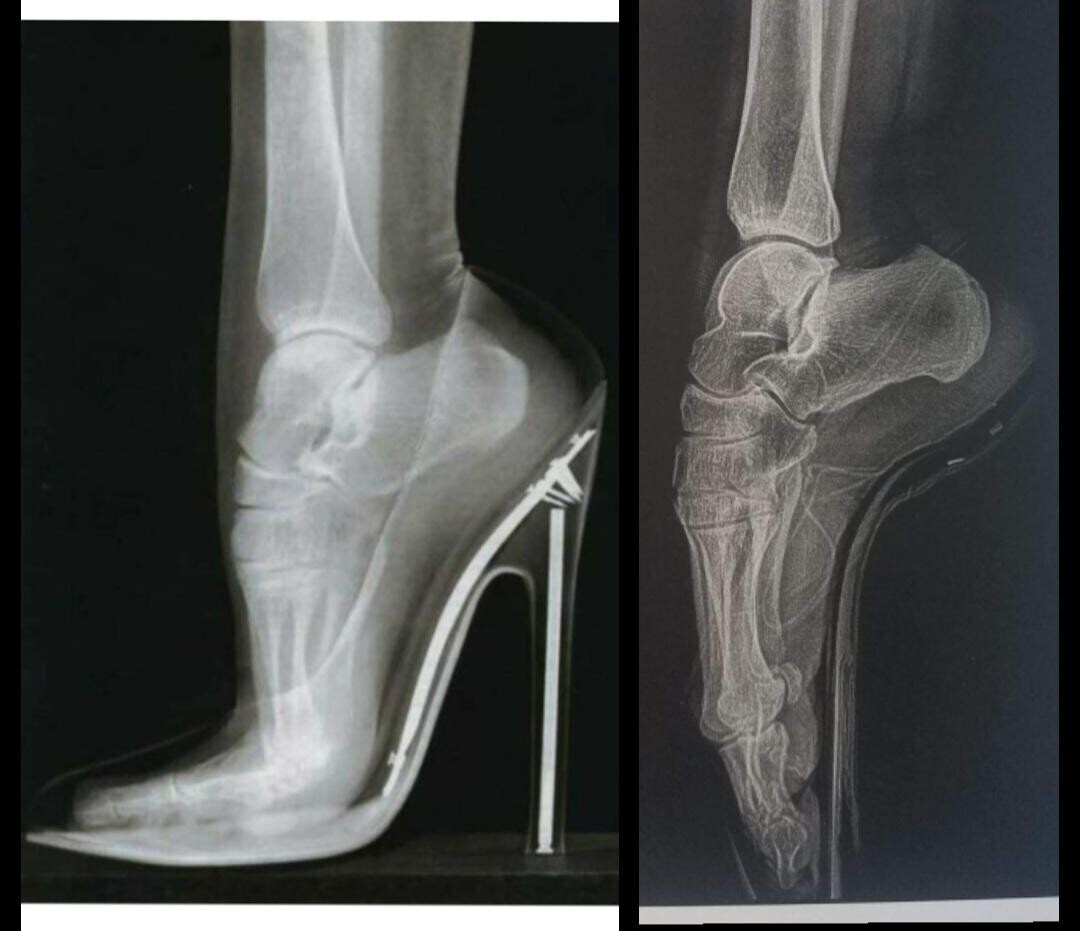

Worked Feet

This is what feet look like in heels and on pointe.